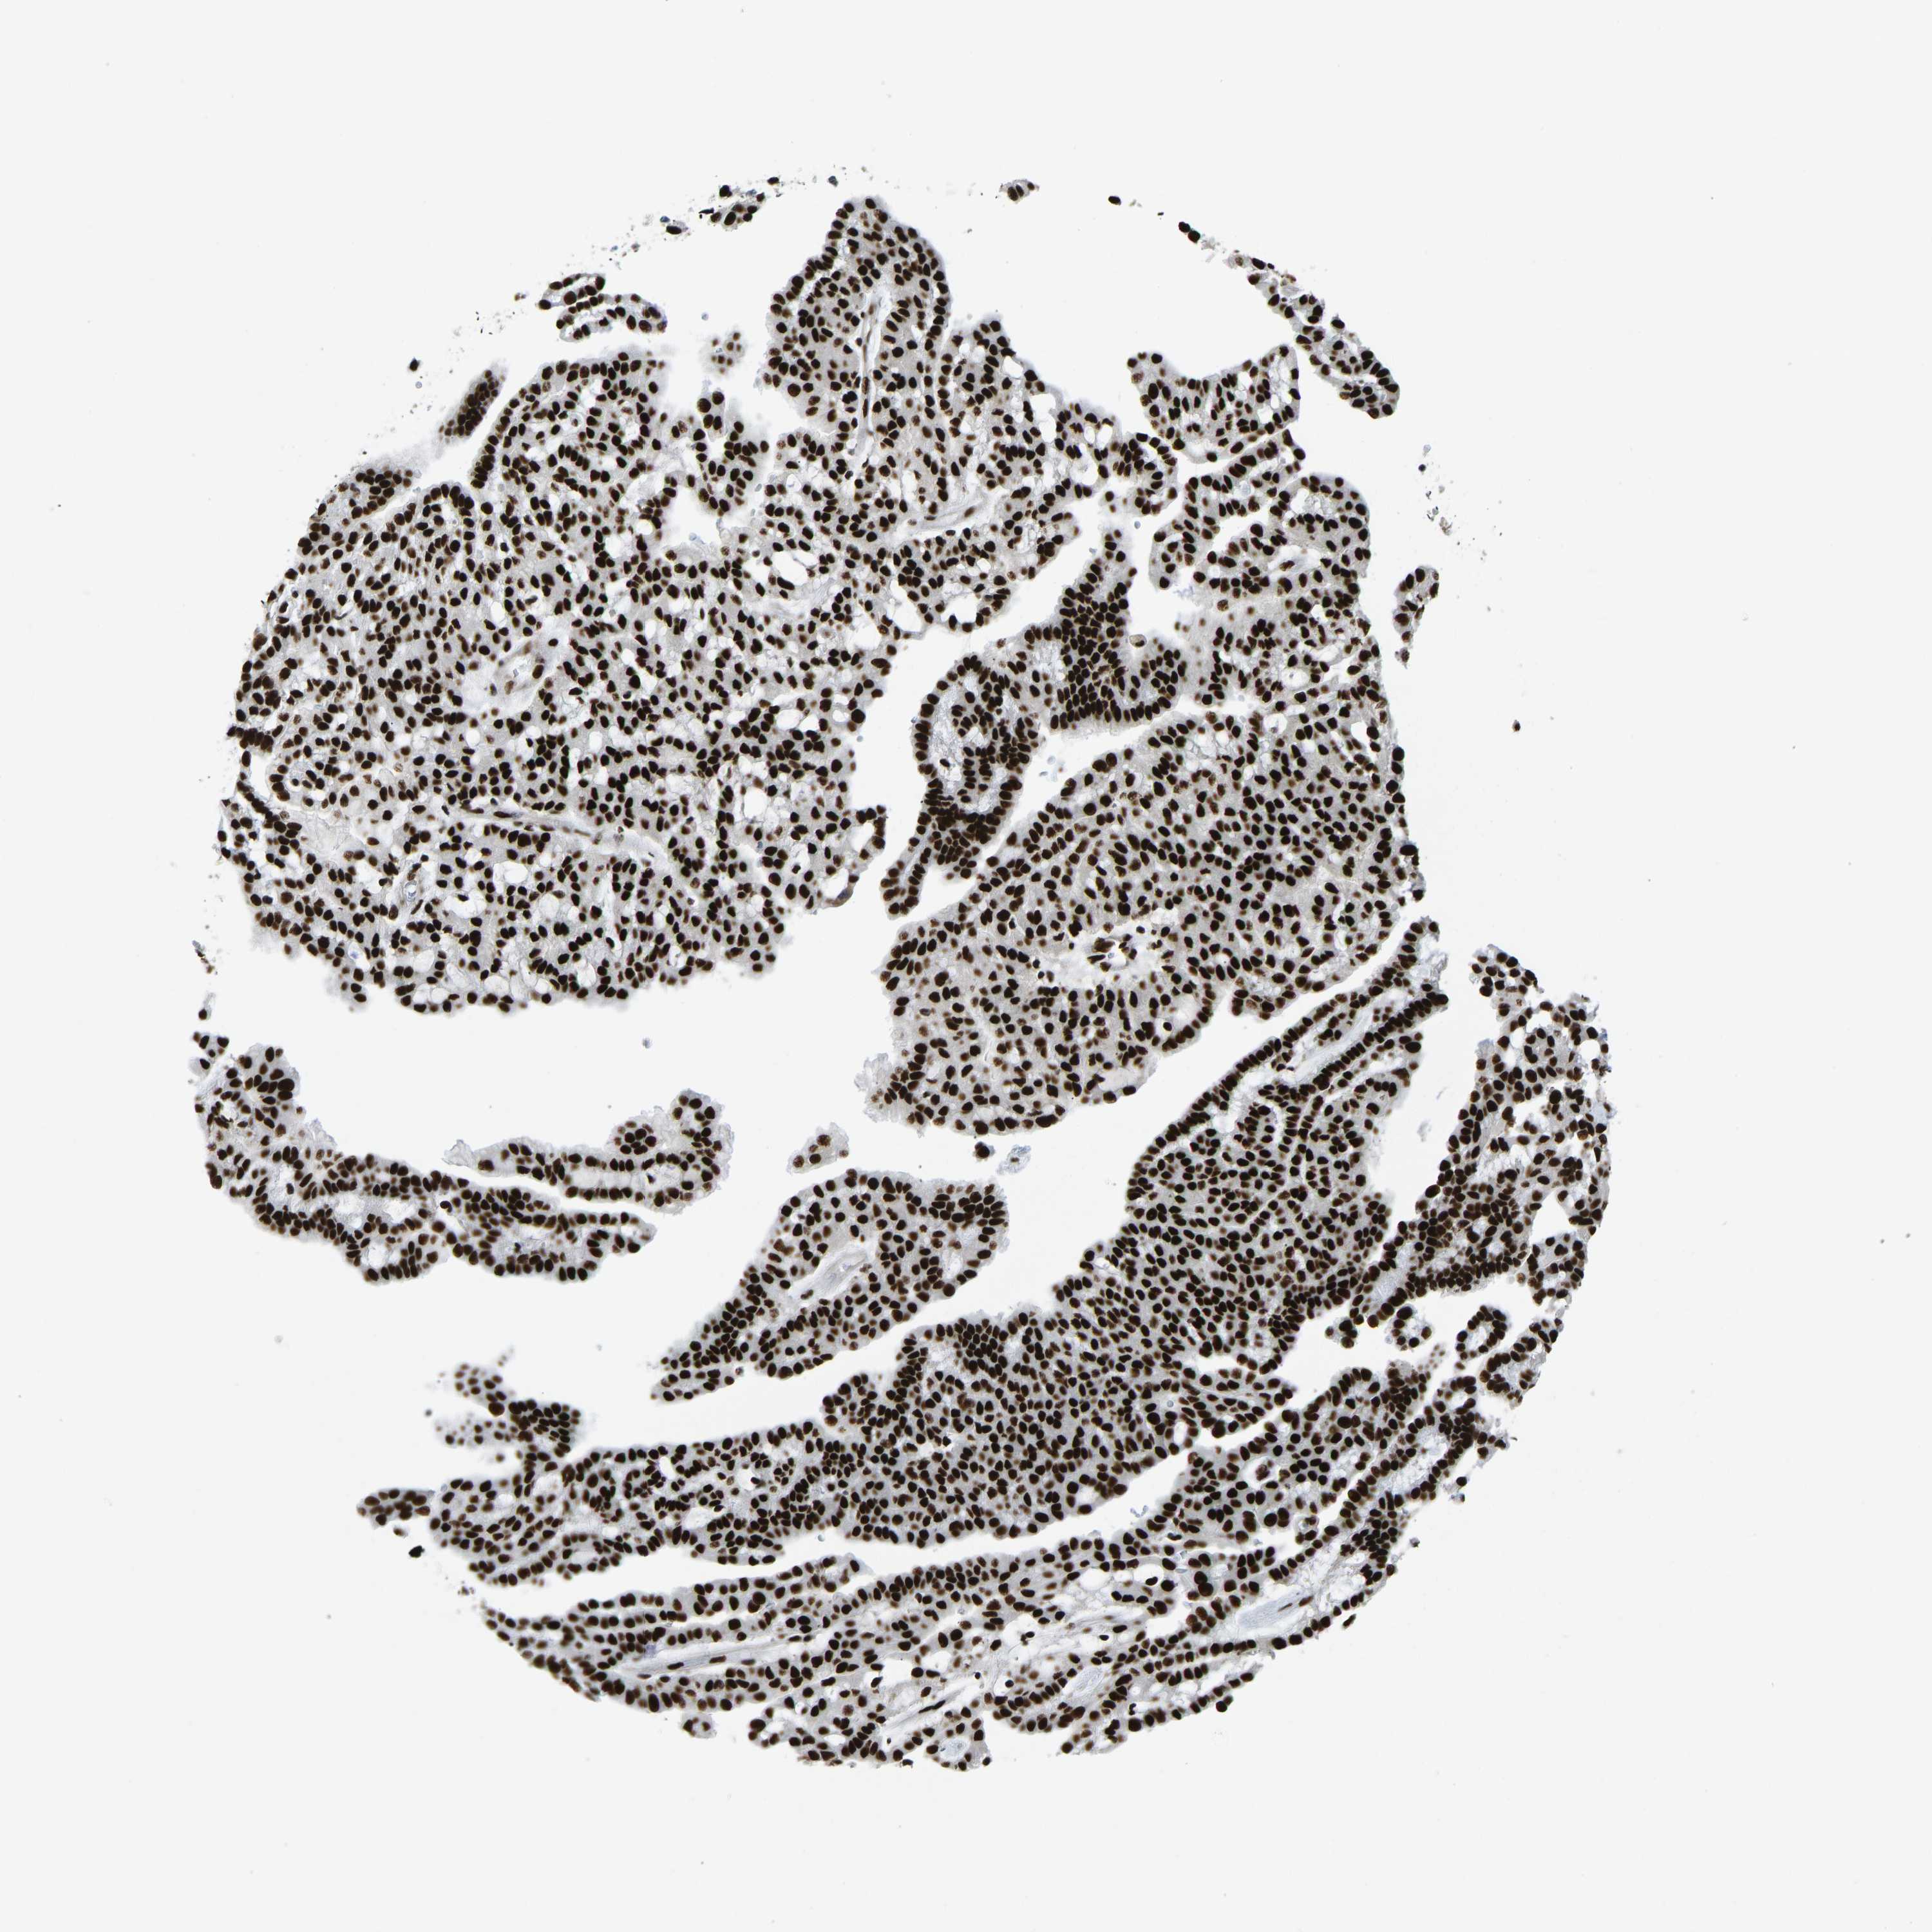

CANCER RENAL CANCER Show tissue menu

KICH TCGA KIRC TCGA KIRC VALIDATION KIRP TCGA PROTEIN RCC CPTAC PROTEIN EXPRESSION